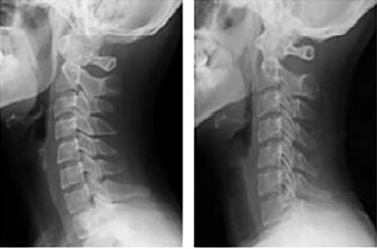

일자목은 경추의 자연스러운 C자 곡선이 무너져, 옆에서 보면 목이 직선처럼 보이는 상태입니다. 정상적인 목뼈의 곡선이 사라져 목이 뻣뻣하게 펴진 모양이 특징입니다.

거북목은 머리가 어깨보다 앞으로 튀어나온 상태로, 측면에서 보면 거북이가 목을 내민 모습과 유사합니다. 경추의 곡선이 무너져 머리 위치가 앞으로 돌출되며, 어깨와 목에 큰 부담이 갑니다.

A. 경추의 곡선 변화와 머리의 위치 차이가 가장 큽니다. 일자목은 C자 곡선이 소실되었지만 머리는 정렬선 내에 있습니다. 반면, 거북목은 머리가 어깨보다 앞으로 돌출됩니다.